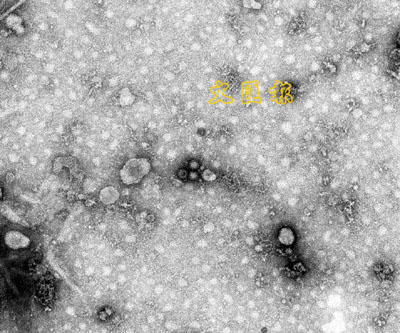

諾沃克病毒

諾沃克病毒因最初於1972年在美國俄亥俄州諾沃克(Norwalk)城胃腸炎患者的糞便中發現而得名。以後又相繼在世界各地發現與該病毒相似的變種,統稱為諾沃克類病毒。